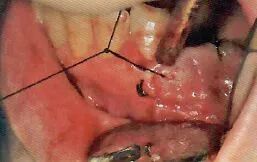

9缝合

切开的牙龈和牙槽粘膜用针缝合

吸唾器的目的

有出血状况时保证缝合部位的术野

缝合时为了避免针尖刺伤粘膜,需要对舌头和颊粘膜进行排开

用针缝合前吸引牙龈

缝合前用吸唾器吸引切开线区域。缝合后,结扎并截断缝合线前,吸引从切口结扎处溢出的血液。

缝合舌侧牙龈时,为了避免患者的舌头触碰到针尖,根据主治医生的喜好可以使用简易的吸唾器,对舌头进行排开。

结扎之后用吸唾器吸引

特别注意,吸引过程可能会引起结扎松动。